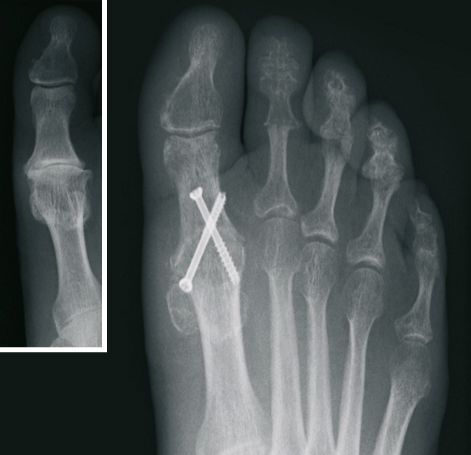

The Hallux valgus (balltoe)

Hallux valgus - in linguistic usage frequently called ball toe - concerns a deviation of the large toe outward, small toes upward. This deformity is more common by women. The exact Cause is not clarified, of course wrong Footwear and hereditary factors play a large role. The different versions are marked by increased deformity and accompanied by pain.

Surgical correction without the presence of pain is not advisable from a purely cosmetic point of view. However, In case of pain in the big toe, the operative procedure is the only permanent therapeutic option.

After extensive examination, consideration of individual needs, as well as analysis of the X-ray images, the treatment is determined. Different internationally recognized surgical procedures are used. We use modern plates and titanium screws.

Depending on the extent of surgery and the procedures to be applied, we have the ability to perform both an outpatient and inpatient treatment.